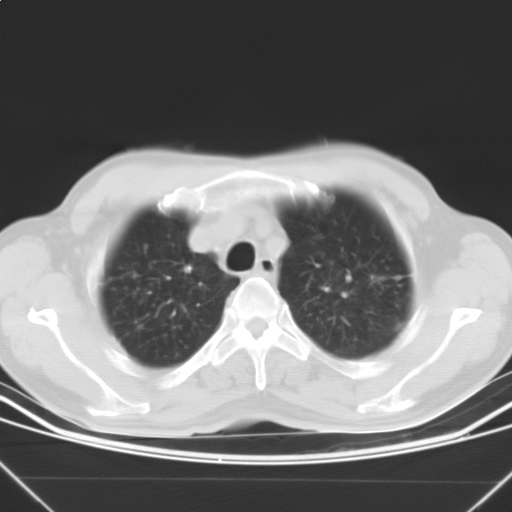

以下是引用随光逐影在2009-5-1 13:53:00的发言:[br]考虑为:1)两肺血行播散型肺结核;2)右肺下叶炎症感染。3)右侧胸膜增厚。